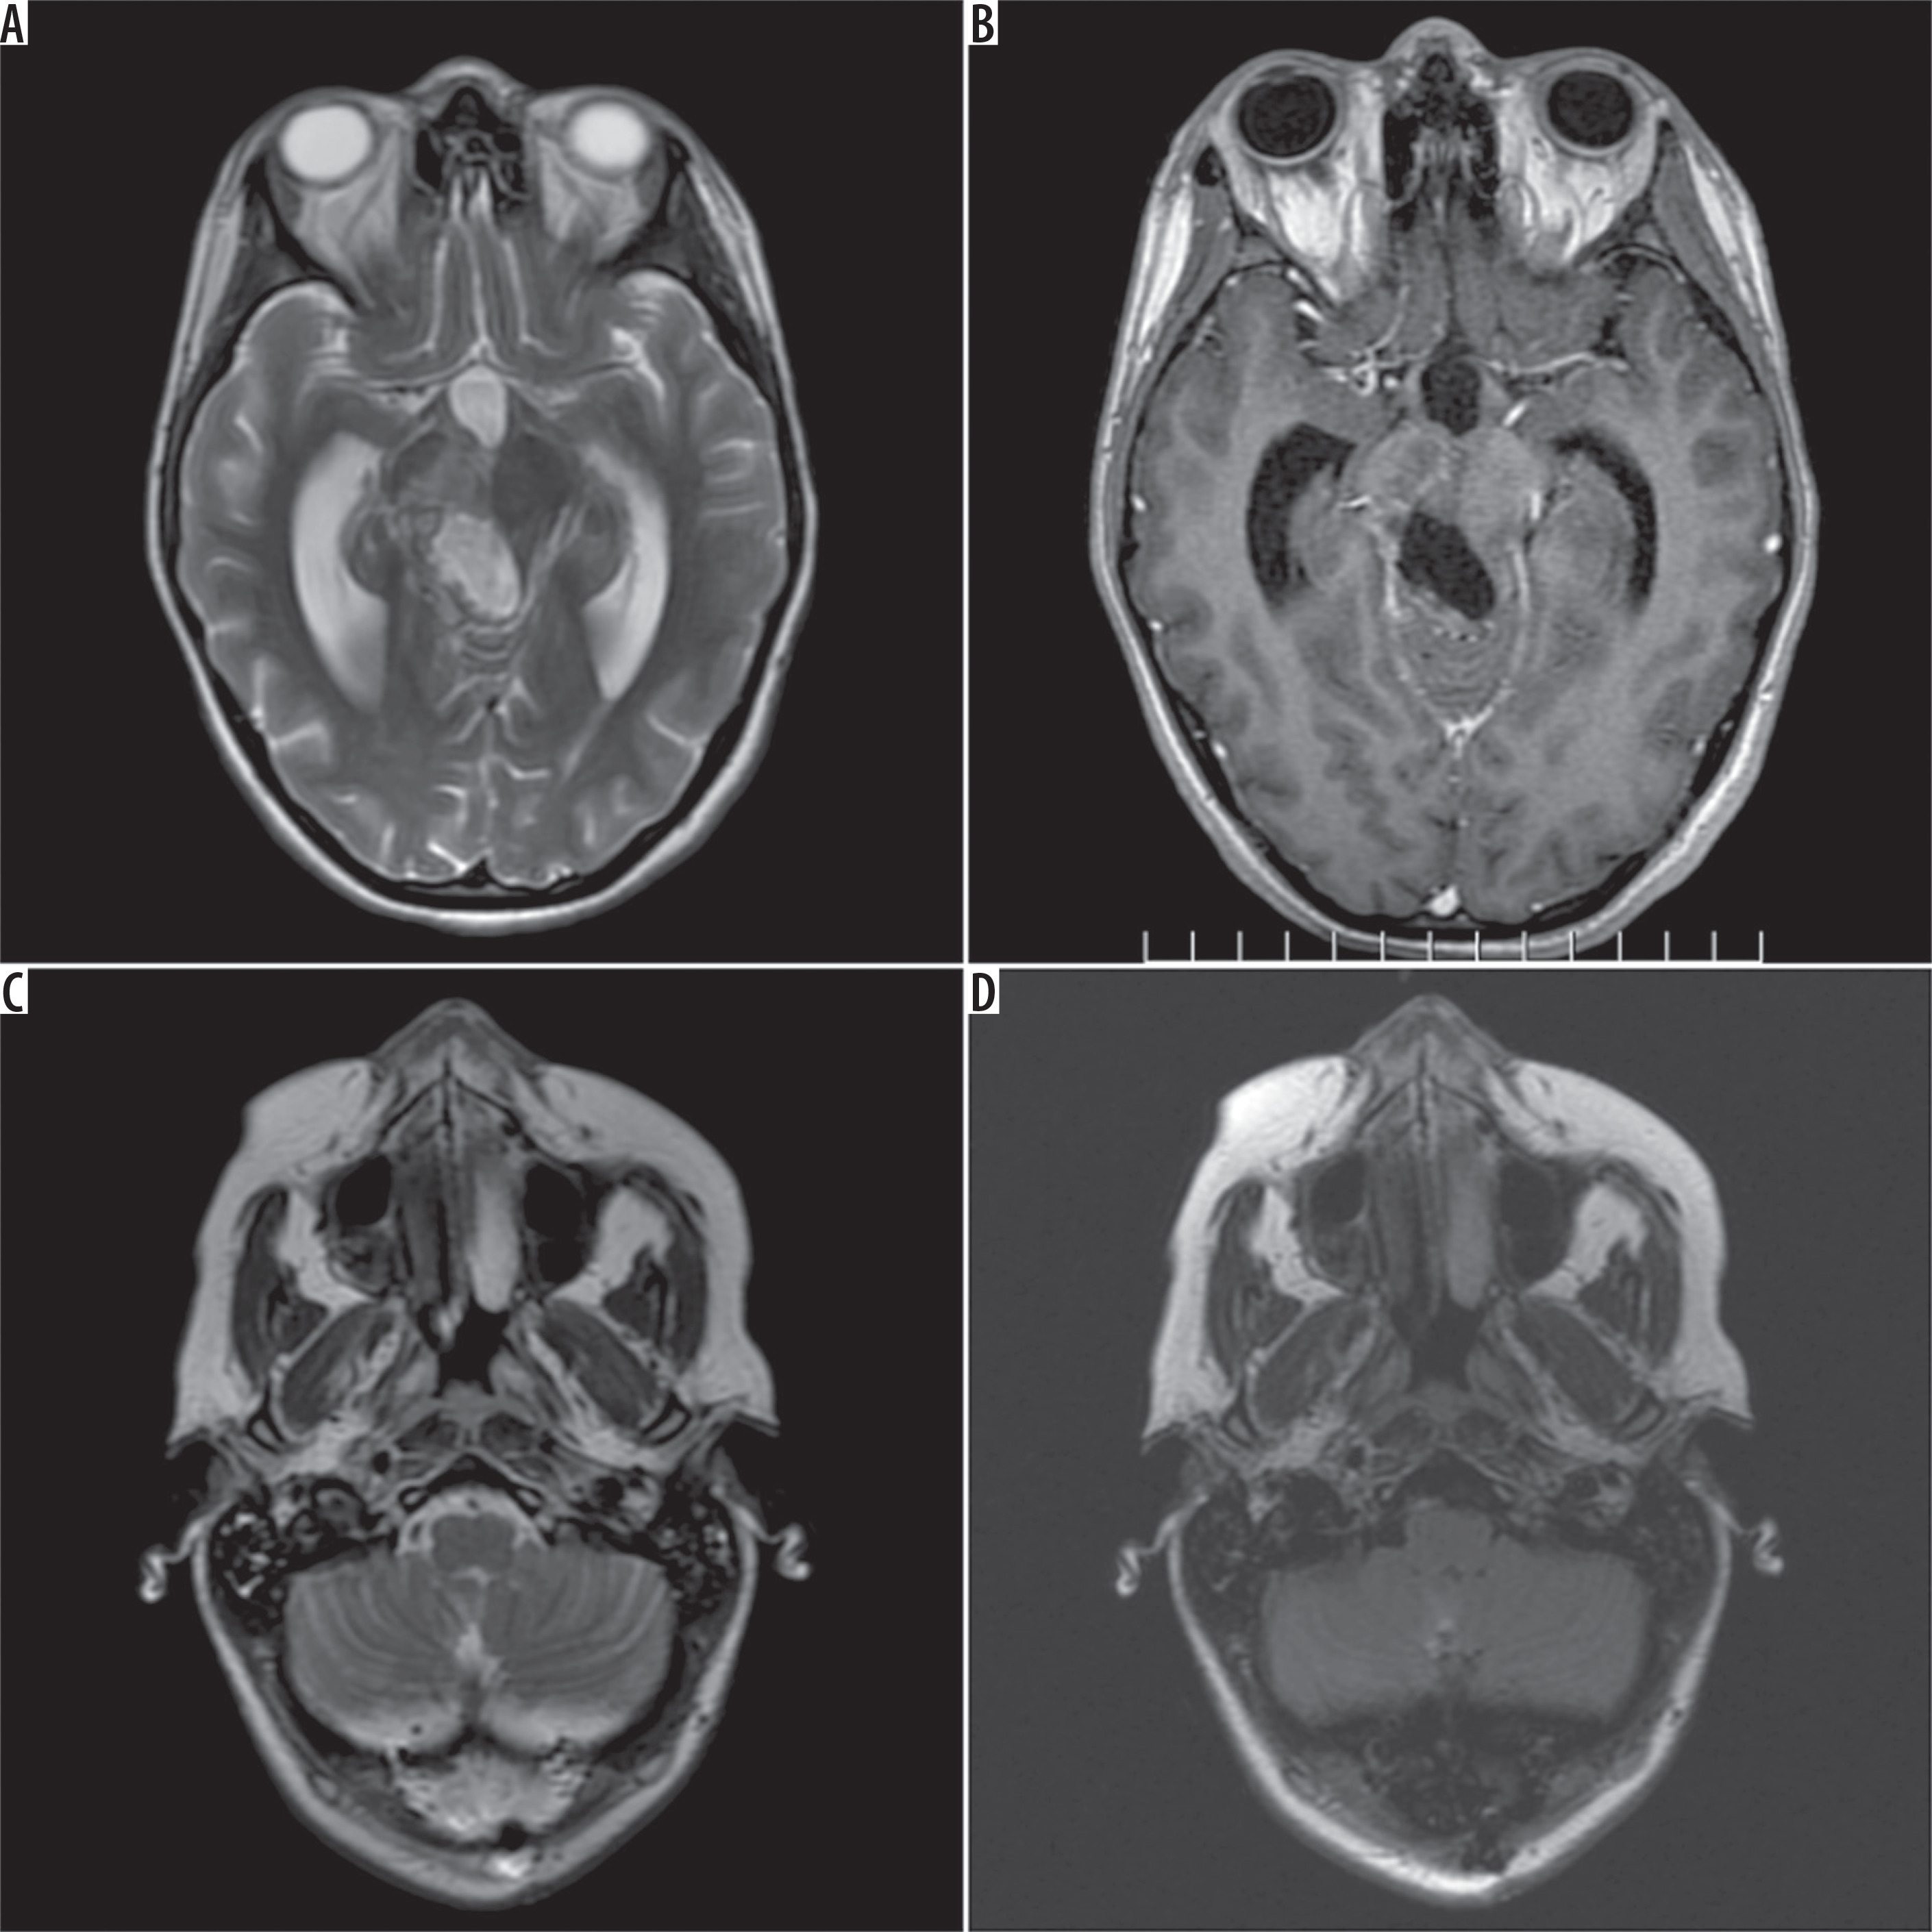

Figure 1

Preoperative magnetic resonance study. Typical features of a pilocytic astrocytoma of the right dorsal part of the brainstem: A) FSE/T2, axial plane, B) FSE/T1 post-Gd, axial plane. No changes at the level of the inferior olivary nuclei: C) FSE/T2, axial plane, D) FLAIR/T2, axial plane